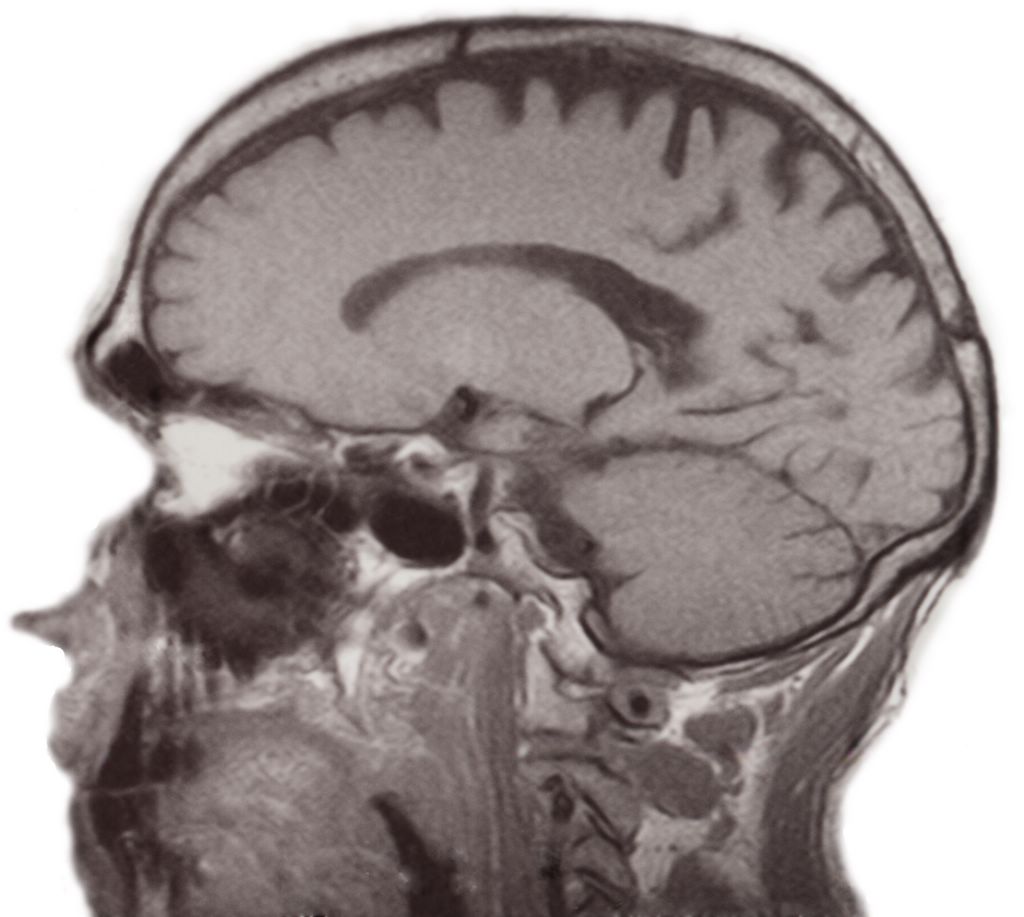

Brains -- mri_8.jpg